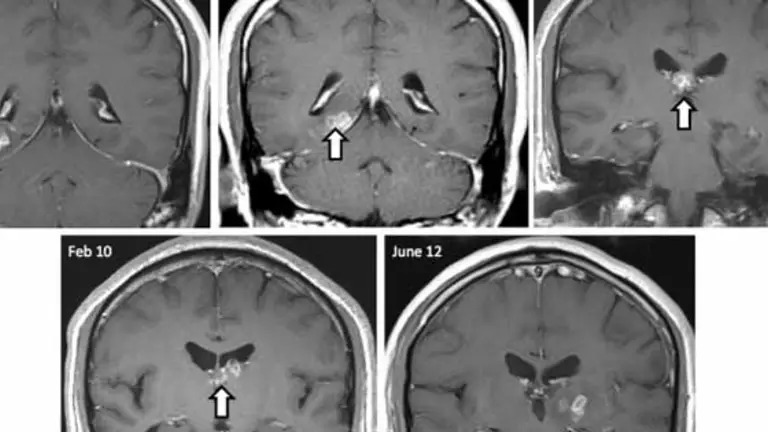

Una biopsia mostró la inflamación en el cerebro del hombre, pero no pudieron determinar la causa exacta de sus síntomas. Tras una biopsia final, los cirujanos desenterraron el origen de los problemas neurológicos del hombre: una solitaria que se había colado en el cerebro del paciente durante los últimos cuatro años.

El parásito había viajado más de 2 pulgadas de la parte derecha del cerebro a la parte izquierda, antes de ser eliminado con éxito a través de la cirugía. Ahora, el paciente está muy bien.